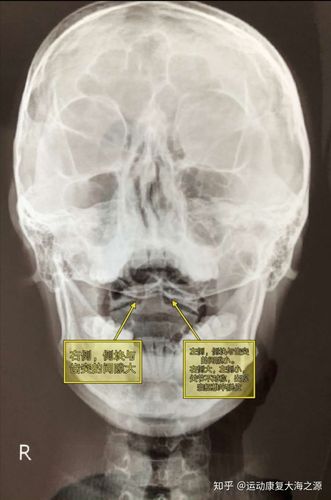

儿童寰枢椎半脱位

儿童寰枢椎半脱位,寰枢椎半脱位牵引图片

儿童寰枢关节半脱位的诊治

寰枢椎半脱位康复案例

小儿寰枢椎半脱位,你了解吗?

寰枢椎半脱位

儿童寰枢椎半脱位图片

寰枢椎脱位图

儿童寰枢椎不对称图

寰枢关节脱位图片

寰椎和枢椎图片

寰椎和枢椎解剖图

寰枢椎

寰枢椎正常图

寰枢椎解剖图

寰枢椎解剖